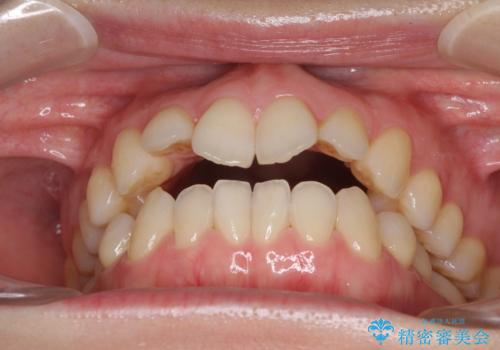

前歯の叢生とオープンバイト インビザラインでの矯正治療

- 前歯の開咬を気にして来院された患者様です。

開咬の治療は、前歯を閉じるように動かすとともに、上下臼歯を圧下(骨内にめり込ませる)させることで進めて行きます。

インビザラインは臼歯の圧下を効果的に行えるため、インビザラインを用いて矯正治療を行うこととしました。

オープンバイトは舌の突出癖により誘発され、治療後も突出癖が残っている容易に後戻りしてしまいます。

治療期間を短縮するためにも、舌突出癖の改善が極めて重要となります。